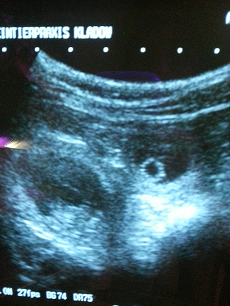

Am 16.10.14 wurde es endlich bestätigt...wir bekommen Welpen!!!

Dipsy hat bis jetzt 6 kg zugenommem

und wiegt jetzt 26 kg ; der Bauchumfang dagegen

ist um 14cm gestiegen von anfangs 64 cm auf nun 80cm